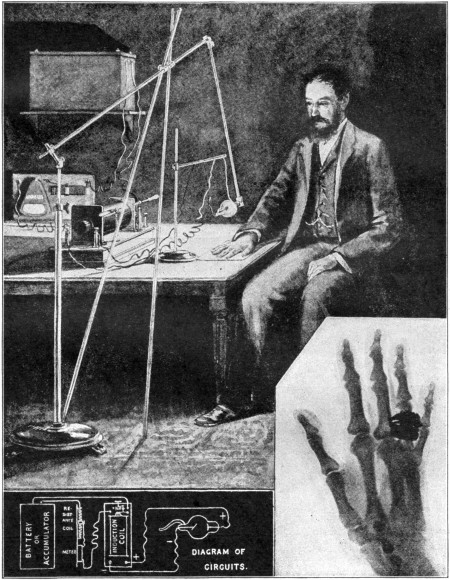

DEVELOPMENT OF THE SCIENCES IN PARALLEL OUTLINES—PRACTICAL MATHEMATICS—Arithematic and its Modern Applications—The Arithmetic of Business, Commercial and Industrial Transactions—Corporations, Stocks and Bonds—Table of Commercial Laws—Weights and Measures—PHYSICS: Laws and Properties of Matter—Mechanics and Inventions—Sound—Heat—Light and Color—Electricity and Magnetism—CHEMISTRY: Theory of Chemistry—Table of the Chemical Elements—The Chemistry of Common Things—REMARKABLE INVENTIONS AND DISCOVERIES—RECENT SCIENTIFIC PROGRESS, X-rays and Radium, Wireless Telegraphy, Wireless Telephone, Aeroplanes, Submarines, Airships, and Explosives.

Picture Diagram Explaining Wireless Telegraphy

Picture Diagram Explaining an Electric Battery

Picture Diagram Showing How Electricity is Generated

Picture Diagram Explaining Radioactivity